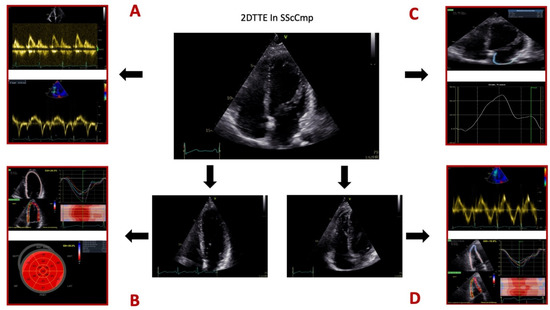

For a summary of different 2DTTE techniques employed for evaluating the SScCmp please see Figure 1.

Figure 1.

Different 2D transthoracic echocardiographic techniques used for evaluating the patients with systemic sclerosis and primary myocardial disease. Legend: Panel (A), mitral valve inflow profile by pulsed-wave (PW) Doppler, Tissue Doppler Imaging (TDI) for myocardial velocities. Panel (B), speckle-tracking echocardiography (STE) for assessing global longitudinal strain of the left ventricle (LV GLS). Panel (C), STE for assessing left atrial (LA) longitudinal strain. Panel (D), right ventricular (RV) evaluation comprised of TDI evaluation of RV free wall systolic velocity and RV free wall longitudinal strain. Images from the personal collection of the authors.